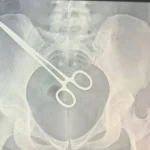

Mulher descobre pinça esquecida dentro de corpo ao passar por raio-x em presídio

Cirurgia ocorreu em setembro deste ano